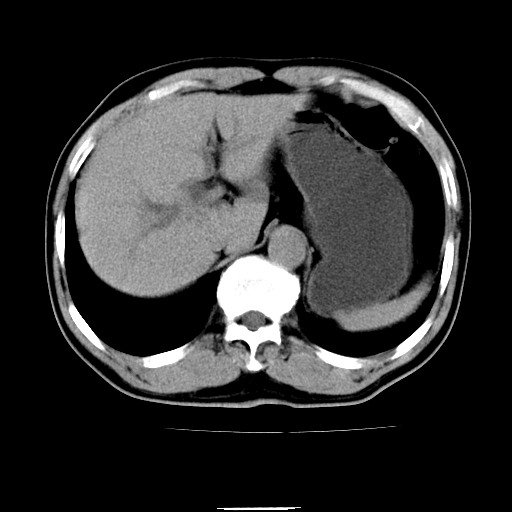

以下是引用chenqiong在2010-3-25 20:56:00的发言:[br]1、胆囊炎,胆囊息肉[br]2、肝内胆管及胆总管扩张,胆总管下端结石[br]3、十二指肠乳头旁憩室

以下是引用zxl51642在2010-3-26 10:47:00的发言:[br]胆囊炎,胆囊息肉,胆总管扩张,但未看到明显肿块,肝内胆管扩张不像恶性,炎性狭窄或阴性结石可能吧,建议mrcp,右肾小囊肿